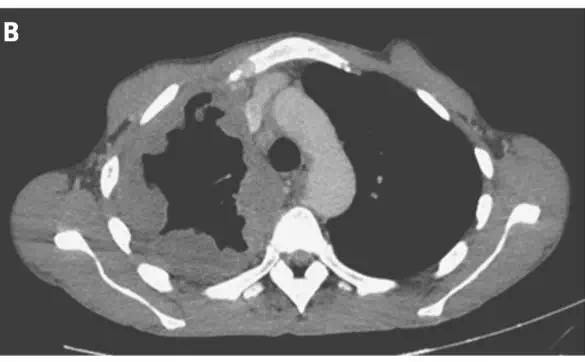

一名40岁男性患者因发热、体重减轻、呼吸困难及咳嗽3个月就诊。体格检查显示前胸壁有一压痛突出肿物,右侧乳头内下方有一小的溃疡性病变(图A)。CT扫描显示胸腔积液(图B)穿透胸壁(图C,箭头),并伴有骨骼破坏。

手术探查发现脓性胸腔积液;胸腔积液培养分离到结核分枝杆菌。自溃性脓胸是胸腔积脓的一种并发症,特点为脓性胸腔积液穿透壁层胸膜进入胸壁。 留置胸管3个月;患者接受利福平、异烟肼、吡嗪酰胺及乙胺丁醇治疗9个月,患者完全康复。